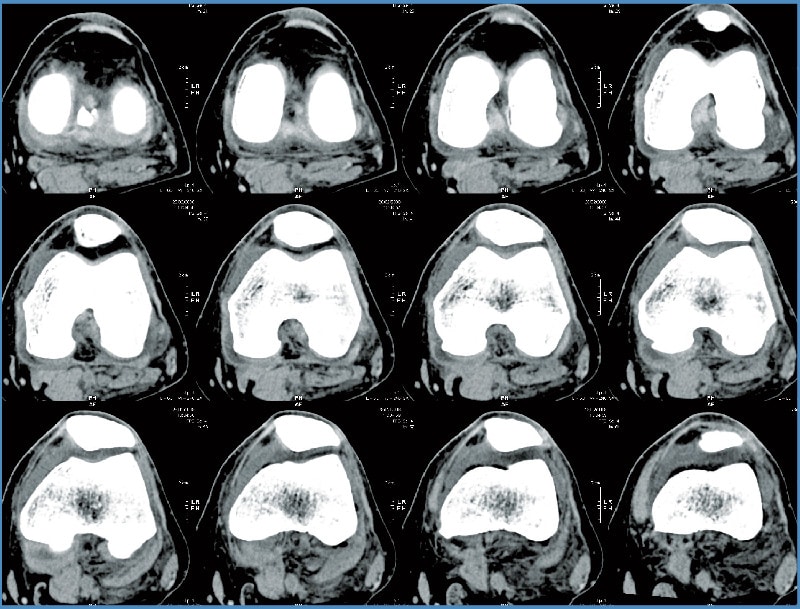

Mako Robotic-Arm Assisted Technology provides you with a personalized surgical plan based on your unique anatomy. First, a CT scan of the diseased hip or knee joint is taken. This CT scan is uploaded into the Mako System software, where a 3D model of your hip or knee is created. This 3D model is used to pre-plan and assist your surgeon in performing your joint replacement procedure.